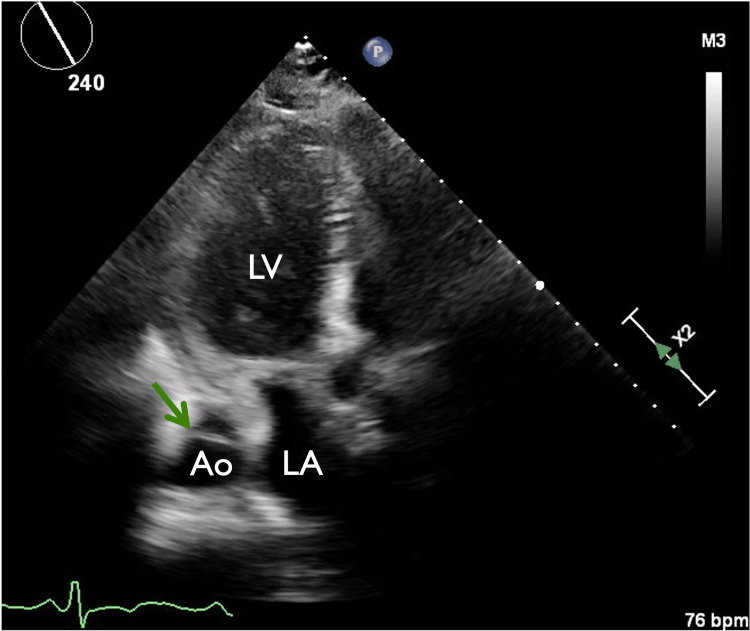

Figure 2. Bedside parasternal long axis view (PLAX).

Bedside PLAX showing dilated ascending aorta with intimal flap (green arrow). There is a moderate pericardial effusion (red arrow) with associated pericardial coagulum (blue arrow). RV: right ventricle, Ao: aorta, LV: left ventricle, LA; left atrium.